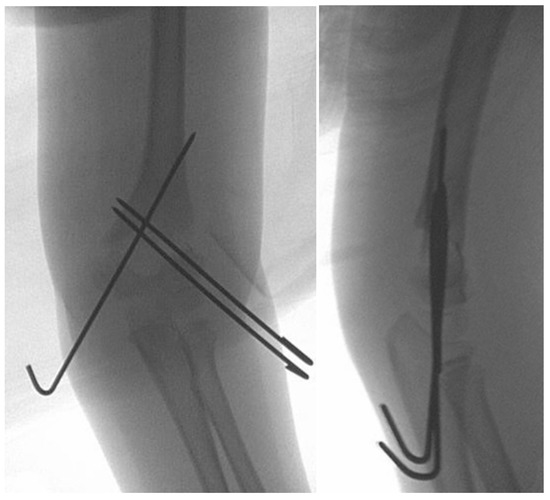

Figure 3. (a) Supracondylar fracture with lateral translation. (b) Reduction achieved via axial traction with the arm in full extension (c).

If skin dimpling is present on the ulnar side, milking maneuvers should be performed. Skin dimpling is a sign that the distal end of the humeral shaft (the proximal fracture fragment) has pierced the muscle and soft tissues around the fracture site. The milking maneuver is performed by the surgeon’s hand “milking” the soft tissues around the humerus in a proximal to distal fashion. This may be performed for 1–2 min until the humerus is felt to be free and mobile, thus allowing the surgeon to proceed with the reduction maneuver. As there is minimal, if any, posterior or anterior displacement, the fracture reduction is best achieved via axial traction of an extended elbow. While the assistant applies countertraction to the axilla, the surgeon provides traction in extension with one hand, while with the other hand applies directed pressure medially or laterally on the distal fragment, thereby correcting the sideward translation as well as the varus–valgus malalignment (Figure 3). AP and lateral fluoroscopic views are achieved by rotating the C-arm around the fracture site, with the patient’s arm stabilized in extension. It is useful to place a rolled towel under the elbow, thus making the lateral imaging easier, providing more room for fracture manipulation, and facilitating fracture fixation in the next step.

The most described reduction maneuver and pinning technique consists of axial traction followed by maximum elbow flexion. Pinning is carried out with the elbow in full flexion [13,20]. The goal of the flexion maneuver is to correct posterior displacement in extension-type fractures. In the sideward displaced fracture, due to the minimal, if any, posterior displacement, there is no need for elbow flexion. In our experience, repeated attempts to reduce the fracture by flexing the elbow led to recurrent failed attempts, displacement of the distal fragment into flexion, and exacerbated rotational malalignment, thereby further compromising the fracture’s stability. Reduction of the fracture is better achieved via axial traction of the extended elbow, with medially or laterally directed pressure on the distal fracture fragment thus correcting the coronal translation and varus–valgus malalignment (Figure 3). The use of a rolled towel under the elbow facilitates control of the reduction in flexion and extension as well as intraoperative lateral imaging.